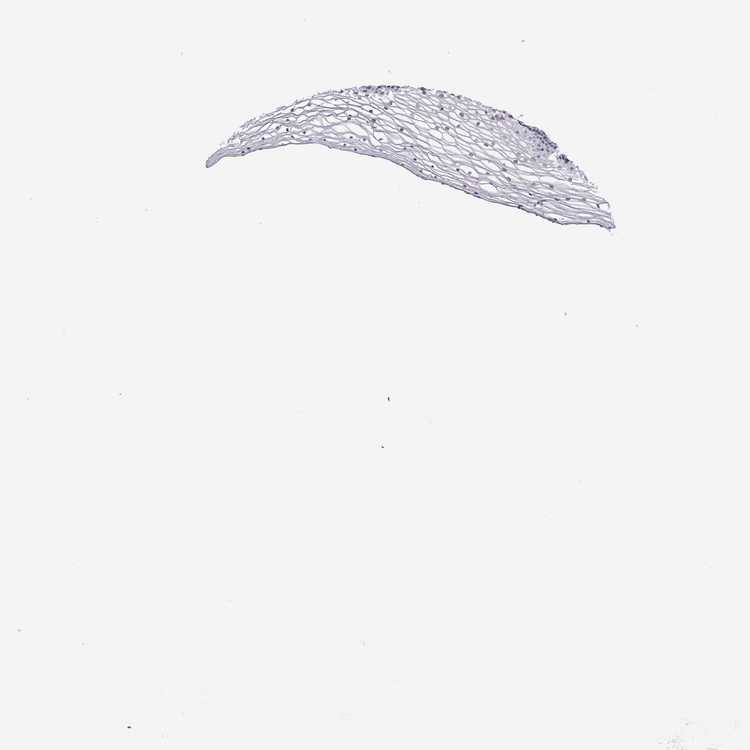

VAGINA - Antibody stainingi

Antibody staining in the annotated cell types in the current human tissue is reported as not detected, low, medium, or high, based on conventional immunohistochemistry profiling in selected tissues. This score is based on the combination of the staining intensity and fraction of stained cells.

Each image is clickable and will lead to virtual microscopy that enables deeper exploration of all samples and also displays staining intensity scores, fraction scores and subcellular localization as well as patient and tissue information for each sample.

Antibody HPA057997

Squamous epithelial cells Not detected